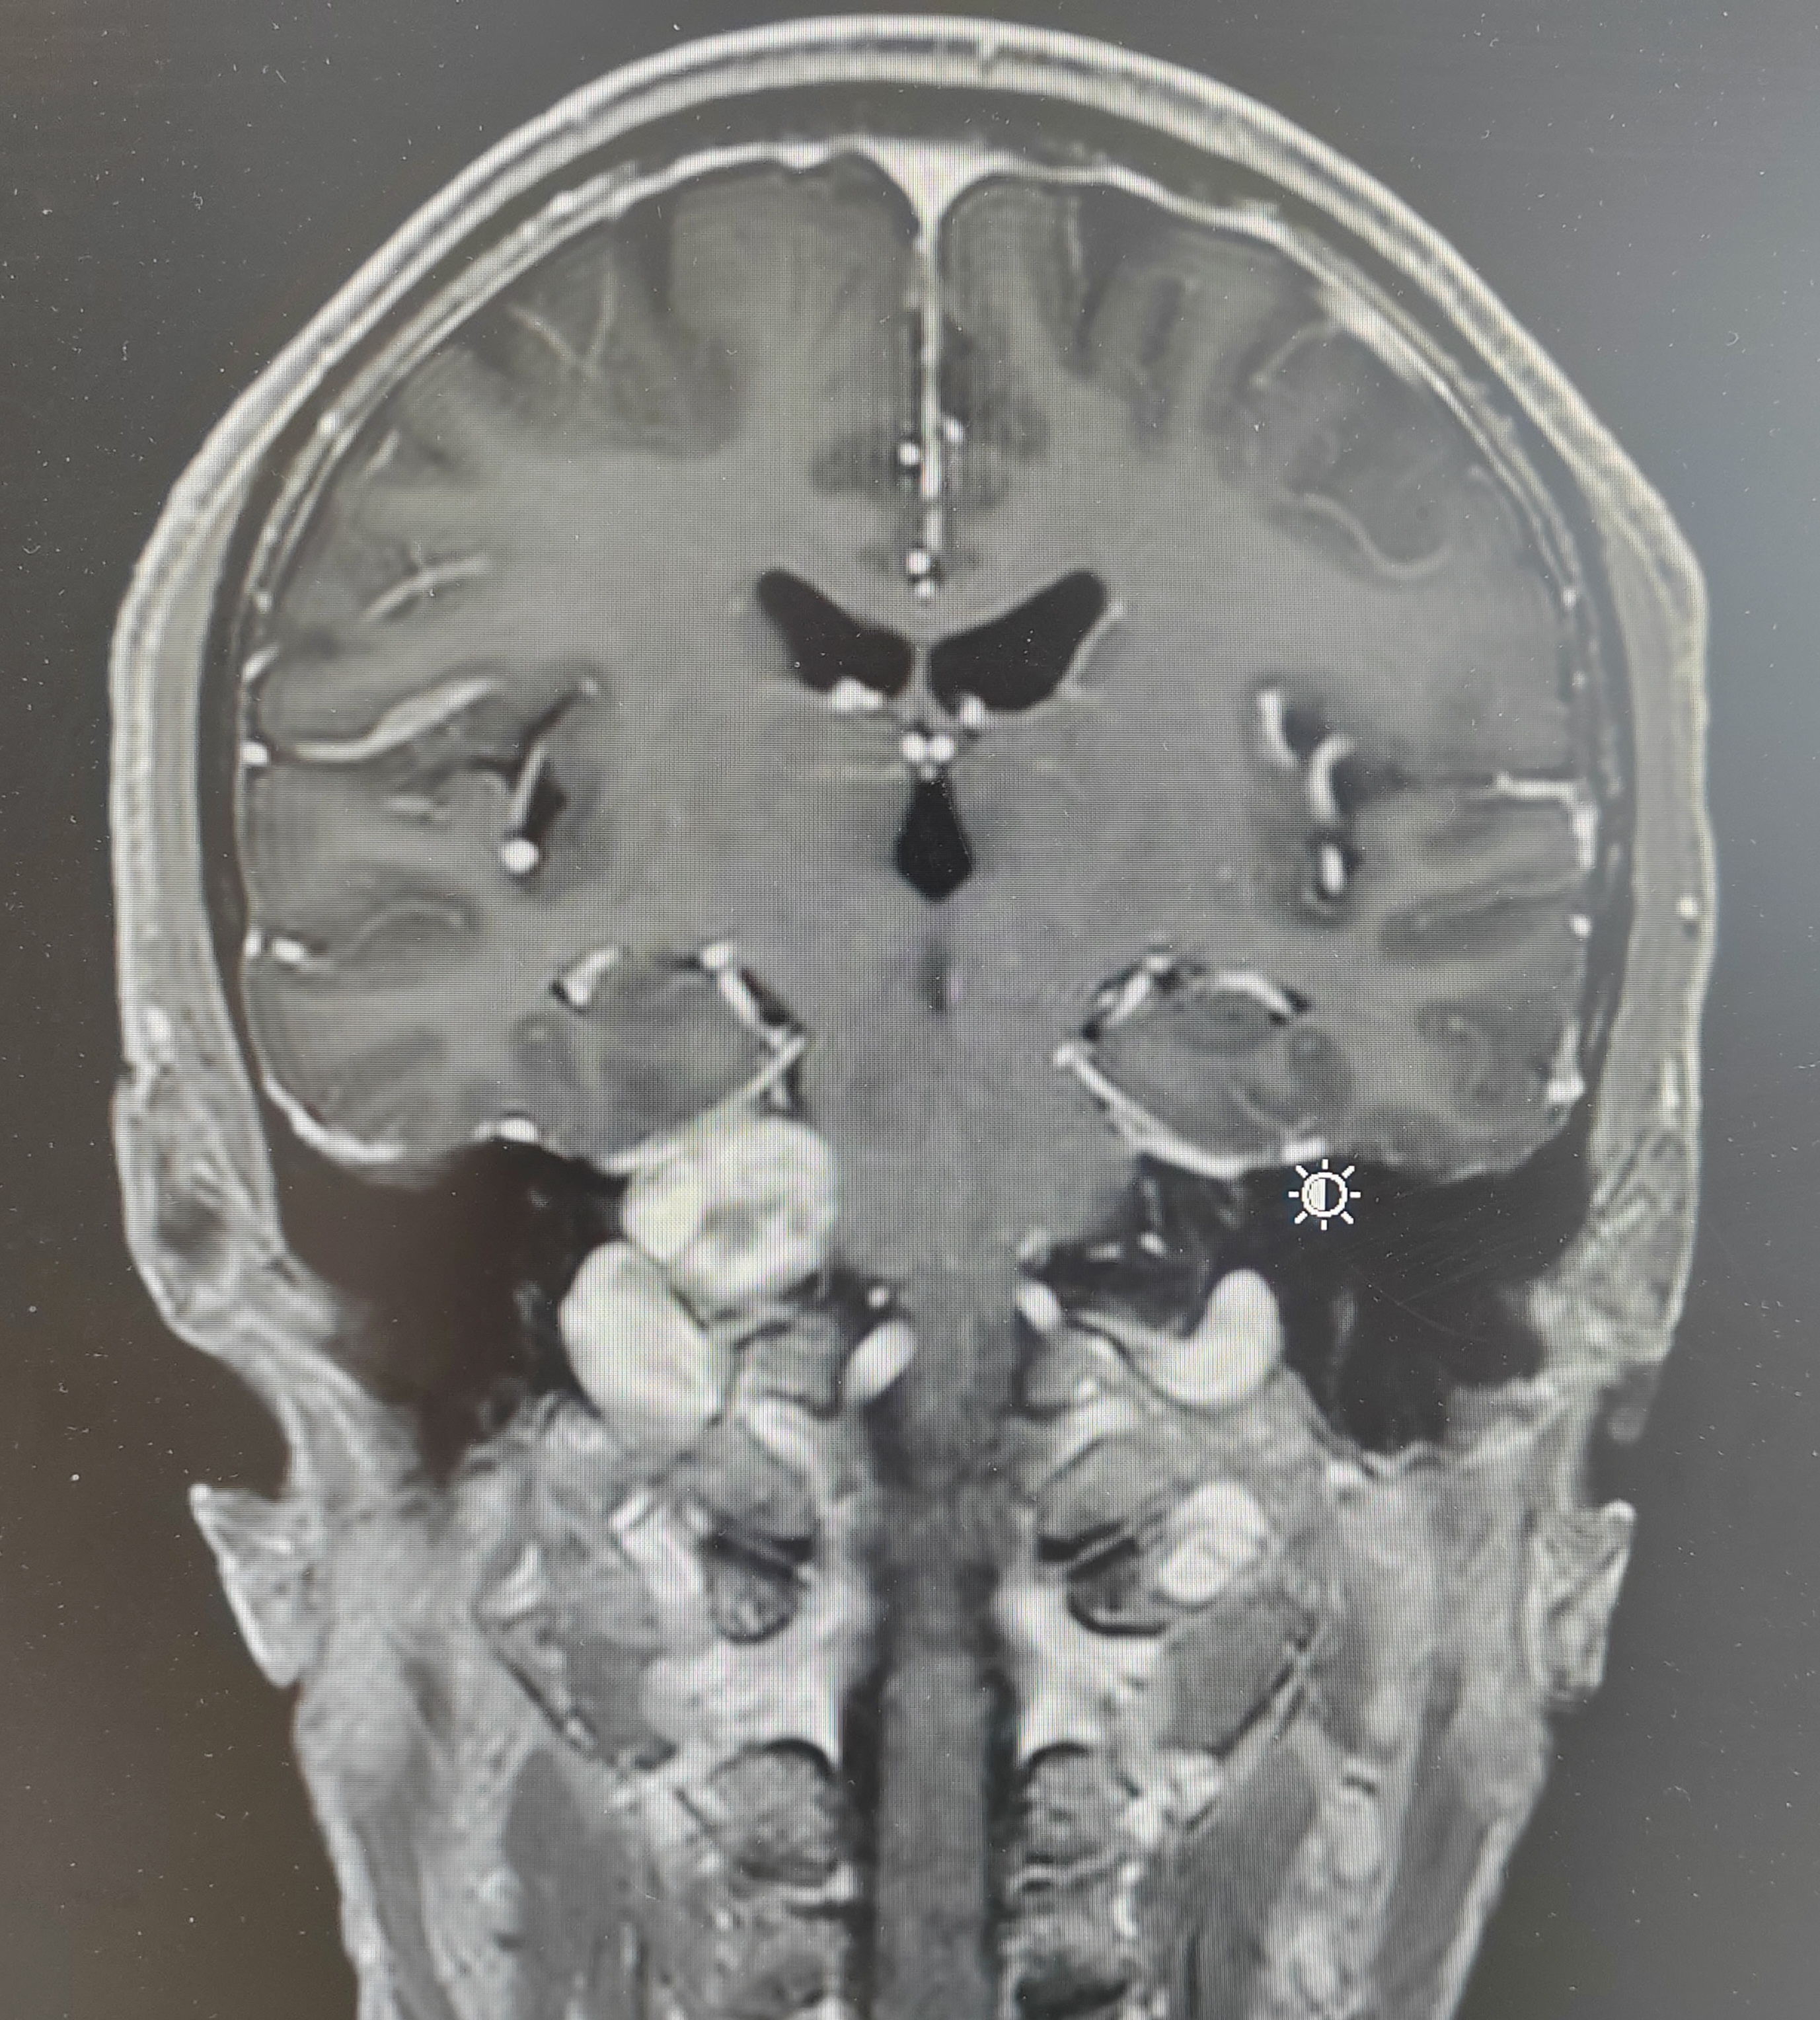

右侧桥小脑角3厘米占位,内听道扩大,肿瘤血供丰富,上方达天幕,与脑干关系密切,蛛网膜间隙不明显,颈静脉球相对高位,诊断考虑:右侧前庭神经鞘瘤(听神经瘤)